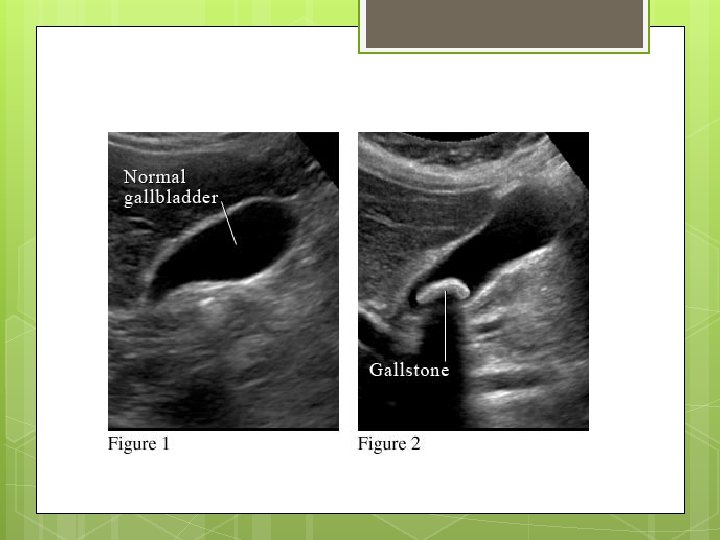

Compare and Contrast from the examination of the Gallbladder Ultrasound identifies if the gallbladder is inflamed If the gallbladder has sludge Measurements Nuclear Medicine Determines if the system being investigated is functioning or not Shows picture not the anatomy Shows bile leakage